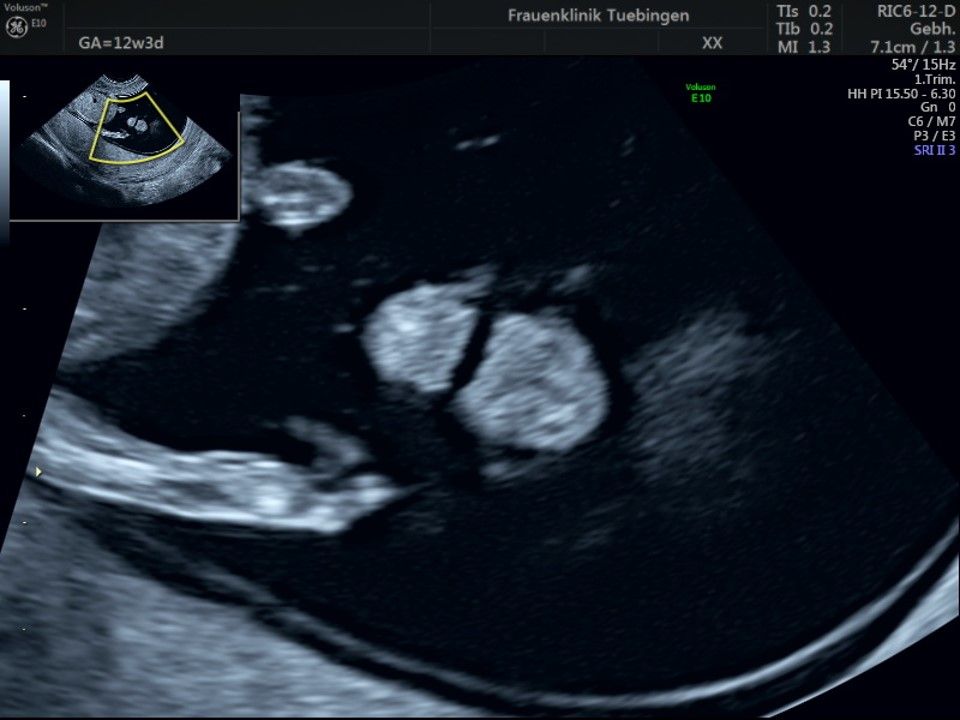

Im Rahmen des Ersttrimester-Screenings untersuchen wir die Organe des Feten mittels Ultraschall. Dabei machen wir auch gerne ein Bild für Sie.

Obwohl der Fet zu diesem Zeitpunkt erst zwischen 5 und 8cm groß ist, lassen sich bereits etwa die Hälfte aller schwerwiegenden Fehlbildungen erkennen bzw. ausschließen. Sollten wir eine Auffälligkeit sehen, werden wir mit Ihnen den Befund und das weitere Vorgehen ausführlich besprechen.

Fetale Anatomie

Herz